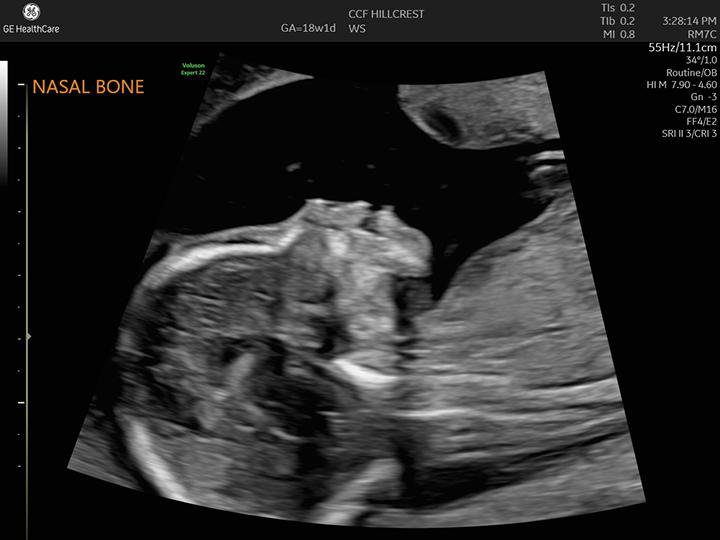

20-Week Ultrasound (Anatomy Scan)

The 20-week ultrasound scan, sometimes called an anatomy or anomaly scan, happens around 18 to 22 weeks of pregnancy. It checks the development of fetal organs and body parts and can detect certain congenital conditions. In most cases, you can also learn the sex of the fetus.

A 20-week ultrasound is a prenatal ultrasound that happens between 18 and 22 weeks of pregnancy. It’s a way to check on how the fetus is growing. It also looks for signs of congenital conditions or how an organ or body part looks.

The scan is one tool your pregnancy care provider uses to make sure the fetus and pregnancy are healthy. It also helps them catch any potential problems before birth. A 20-week ultrasound is also called an anatomy scan.

During your appointment, an ultrasound technician (sonographer) takes pictures and measurements of the fetal:

- Lips, chin, nose, eyes and face